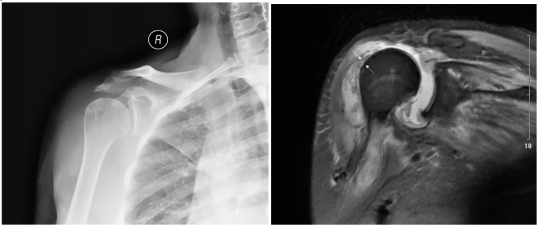

一位52岁女性因发烧、喉咙痛、急性严重右肩疼痛伴烧灼感、红肿入院。患者有高血压、高脂血症、肾结石和肾积水的病史,为此每天服用苯磺酸左旋氨氯地平和阿托伐他汀钙。患者无任何感染性关节炎的常见危险因素,如免疫抑制、糖尿病、近期创伤或手术。六年前,患者感到右肩慢性疼痛,活动受限。大约在急性发作前一个月,她在当地诊所接受了5次右三角肌注射曲安奈德,以缓解最近恶化的疼痛,之后症状暂时缓解,同时出现反复发热。最后一次给药后两天,患者肩关节剧烈疼痛,被动活动极少,局部皮肤温度升高,出现红肿,喉咙痛。右肩关节X线片检查发现右肩关节退行性变(图1)。

图1. 后前视图显示退行性改变

图2. 右肩MRI显示冈上肌腱撕裂(箭头)和巨大脓肿。

为了进行全身治疗,患者被转诊到骨科。MRI结果显示肩关节脓肿(图2)。从关节中取出26ml红色脓液(正常范围0.1-2ml),随后进行分析。细胞数量为46000个/mm3(正常范围200–700/mm3)、97%为多形核(PMN)白细胞(正常范围 < 25%),阴沟肠杆菌阳性,真菌培养试验为阴性。